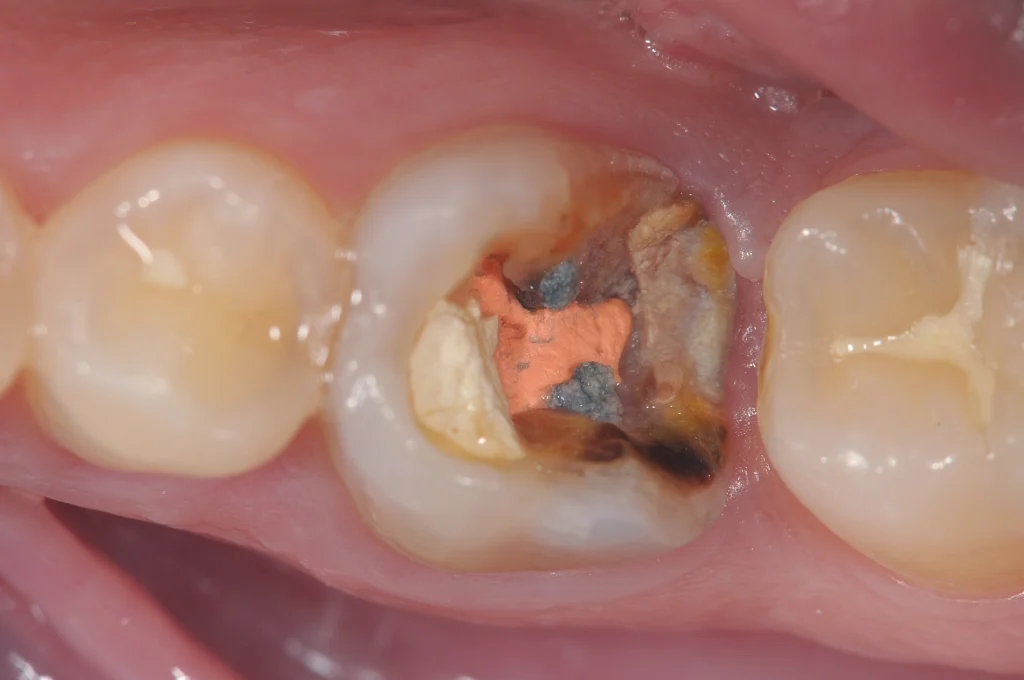

Una capsula dentale è generalmente necessaria quando il dente è gravemente danneggiato da carie, fratture o lesioni, oppure dopo una cura canalare. In questi casi, la capsula provvisoria è spesso utilizzata inizialmente, in attesa della protesi definitiva.

- Carie gravi: Quando la carie è estesa e ha compromesso la struttura del dente, una capsula è necessaria per restaurarlo completamente.

- Dente devitalizzato: Un dente che ha subito una cura canalare può essere indebolito, e una capsula aiuta a proteggerlo.

- Rimozione del materiale danneggiato: Durante la prima visita, il dentista rimuove la parte danneggiata del dente per creare lo spazio adeguato alla capsula.